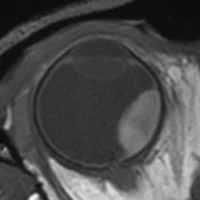

New MRI technologies to improve the care for eye cancer patients.

Through MRI-based radiotherapy planning we aim to preserve more of our patients’ vision.